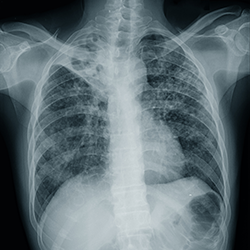

Imaging and Pathogen Interpretation

Two main radiographic techniques are used to assist in the diagnosis of CAP: chest x-ray (CXR) and chest CT. CXR is often the initial imaging modality because it is relatively inexpensive and readily accessible. However, the sensitivity (median, 70%; range, 16%-95%) and specificity (median, 55%; range, 0%-94%) vary according to the quality of the image, as well as the ability to compare current with prior images.3 The sensitivity also is lower in immunocompetent patients who have evidence on chest CT but not on CXR (eg, older adults).1

Chest CT is a more sensitive diagnostic imaging technique that is capable of revealing findings suggestive of pneumonia up to 5 days earlier than CXR. It can also assist in differentiating the radiological patterns present, which can aid in determining the etiologic agent.1

Although the radiographical findings may vary pending modality used and immunocompetency of the patient, bacterial, viral, and fungal pneumonias have different imaging results. Findings include:

- bacterial infections with lobar consolidation;

- viral infections with bilateral, diffuse infiltrates; and

- fungal infections with nodular/cavitary lesions (particularly in the upper lobes), halo sign/reverse halo sign, and/or mediastinal lymphadenopathy.11